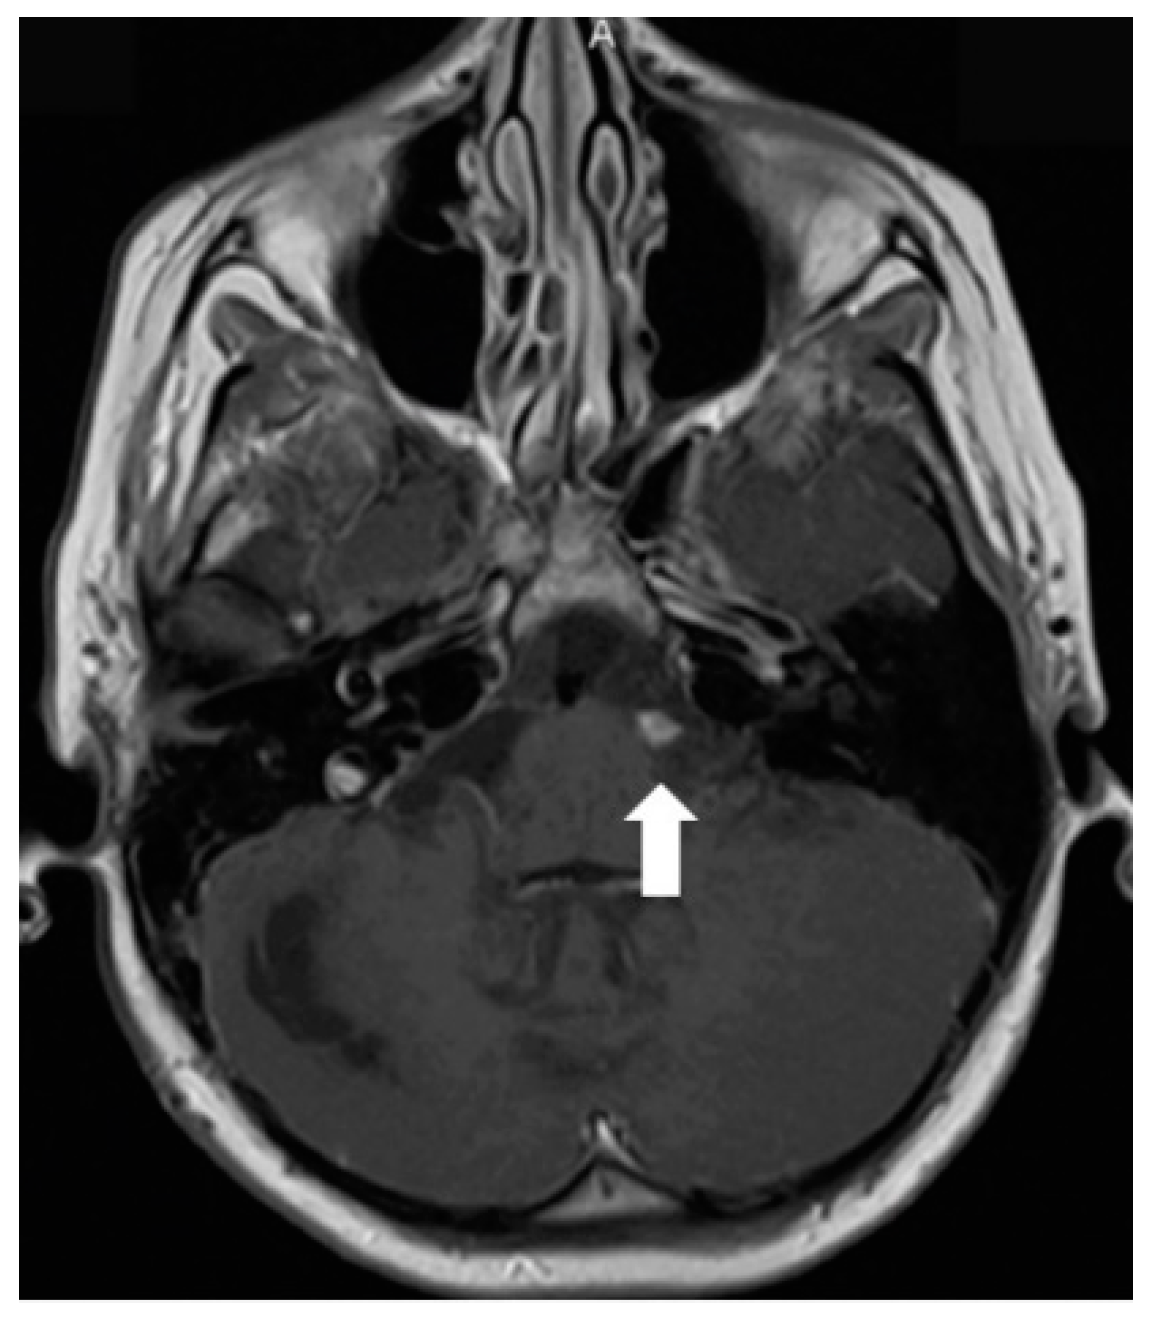

After 4 months when symptoms of raised intracranial pressure recurred, additional findings were detected on follow-up MRI. Most of the subarachnoid cisterns, Sylvian fissures, sulci of superior parts of the cerebellum, and the lower part of the fourth ventricle were filled with diffuse non-contrast-enhancing multiple small cyst-like lesions (Figure 3). These lesions were more evident on T2W/FLAIR and T2W/SPC images; T2W/FLAIR revealed iso/slightly hypointense lesions resembling cysts in the previously mentioned areas. The lesions did not show diffusion restriction or any significant compression of adjacent structures. Additionally, magnetic resonance spectroscopy of the lesion demonstrated lactate peak. Due to the uncertain origin of the findings, a biopsy of the newly detected tissue in the perimesencephalic cistern was performed. Histological appearance and immunohistochemical phenotype of the sample were the same as in the previous examination, consistent with subarachnoid spread.

Figure 3.

Follow-up MRI of the brain 1 year after the onset of the symptoms (April 2012): (A) Axial T2W/FLAIR/FS and (B) T2W/SPC images disclose masses composed of multiple small cysts in the subarachnoid cisterns, Sylvian fissures, and cerebellar sulci. There is no contrast enhancement (C) in the referred areas.

Later the girl was treated in Klaipeda University Hospital. In May 2013, a follow-up MRI demonstrated enlarged cystic lesions in the subarachnoid spaces with compression of the brainstem and the cerebellum and vivid leptomeningeal enhancement extending to the spinal canal (Figure 4). T2W/FLAIR/FS images revealed heterogenous, slightly hyperintense lesions with hypointense foci in the subarachnoid spaces. Clinically, ataxia and weakness of the legs worsened. Partial resection of the neoplastic masses from premedullary cisterns and the IVth ventricle was performed. It was decided to administer chemotherapy with temozolomide. Gradually, the condition of the patient improved.

Figure 4.

Follow-up MRI of the brain 2 years after the onset of symptoms (May 2013): (A) Axial T2W/FLAIR/FS, (B) axial, and (C) sagittal T1W postcontrast images demonstrate enlarged cystic lesions in the subarachnoid spaces causing compression of the brainstem and the fourth ventricle and vivid leptomeningeal enhancement extending to the spinal canal.